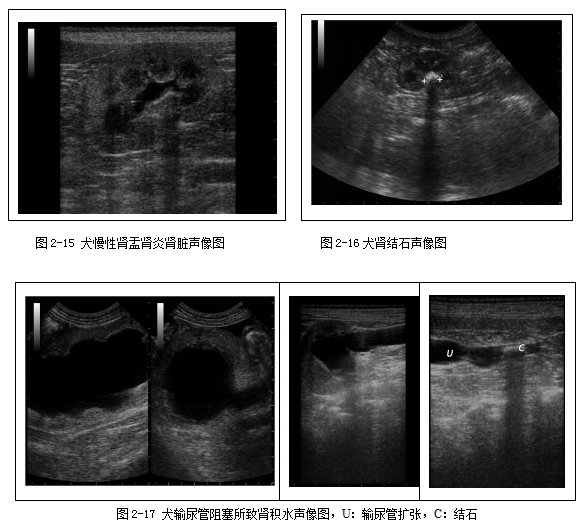

泌尿系统超声检查主要用于评估膀胱的病变(图2-9、2-10、2-11)和肾脏损失(2-12、2-13、2-14、2-15、2-16),以及输尿管的扩张(图2-17)。